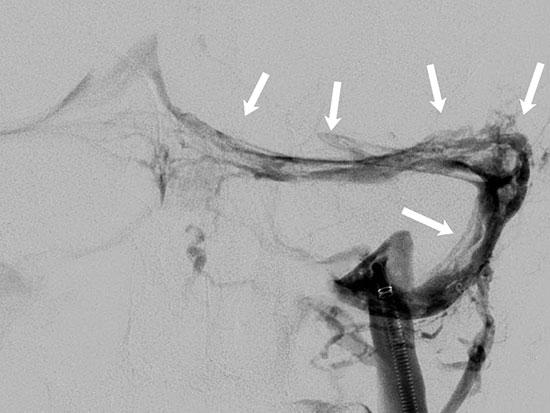

Angiogram images show blood vessels following thrombectomy and treatment with blood thinners.

The arrows indicate scattered blood clots present throughout the venous system, which were diminished in size and extent after treatment.Fisher initially treated Thomas’ blood clots with blood thinners, hydration and pain